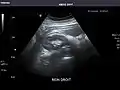

Kidneys: Right and left kidneys measure 11.5 cm and 12 cm in length respectively. No hydronephrosis. Small left lower pole kidney cyst.

Right kidney